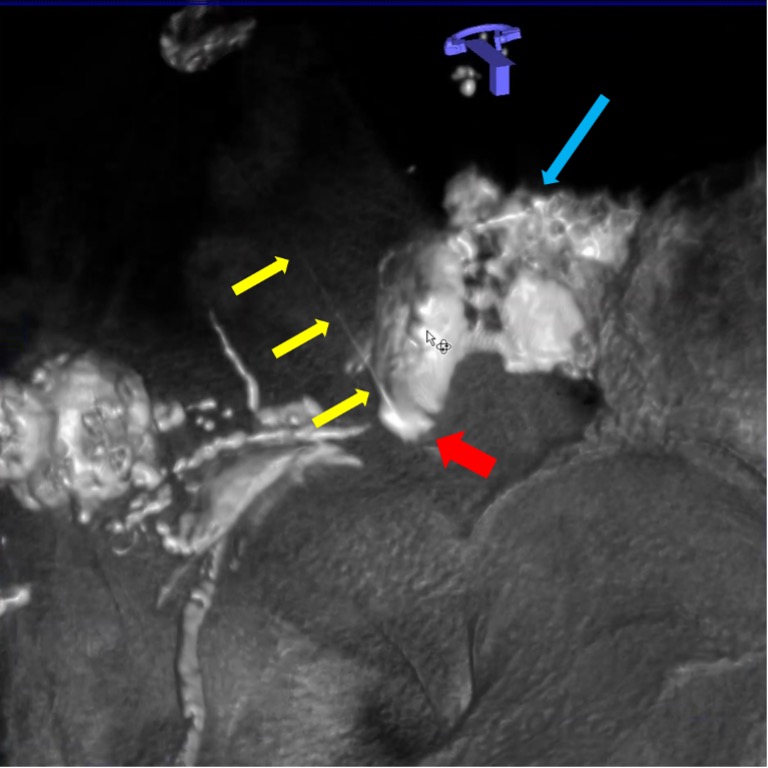

Рис. 2. Интранодальная паховая ПДКТ-лимфангиография с последующей чрескожной пункцией лимфопсевдоаневризмы (толстая красная стрелка) иглой 25 G (0,5 мм) (тонкие желтые стрелки) с целью эмболизации массивной послеоперационной тазовой лимфореи (длинная синяя стрелка): ПДКТ позволяет отчетливо визуализировать пункционную иглу на реконструированных изображениях и точно определить положение ее дистальной части.